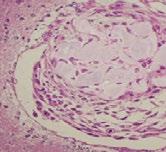

STIMULATING BLOOD VESSEL FORMATION WITH MAGNETS

A magnetic field can be used to stimulate blood vessel growth, according to a study published in the journal Science and Technology of Advanced Materials. The findings, by researchers at the Técnico Lisboa and NOVA School of Science and Technology in Portugal, could lead to new treatments for cancers and help regenerate tissues that have lost their blood supply.

“Researchers have found it challenging to develop functional, vascularized tissue that can be implanted or used to regenerate damaged blood vessels,” says Frederico Ferreira, a bioengineer at Técnico Lisboa’s Institute for Biosciences and Bioengineering. “We developed a promising cell therapy alternative that can non-invasively stimulate blood vessel formation or regeneration through the application of an external low-intensity magnetic field.”

The researchers worked with human mesenchymal stromal cells from bone

marrow. These cells can change into different cell types, and also secrete a protein called VEGF-A that stimulates blood vessel formation.

The research team, including Ana Carina Manjua, Frederico Ferreira, and Carla Portugal, developed two hydrogel supports made of polyvinyl alcohol (PVA) and gelatin, both containing iron oxide nanoparticles. Cells were then cultured on the hydrogels and exposed to a low-intensity magnetic field for 24 hours.

The cells on the PVA hydrogel produced less VEGF-A after the magnetic treatment. But the cells on the gelatin hydrogel produced more. Subsequent lab tests showed that these VEGF-A -rich extracts improved the ability of human vascular endothelial cells to sprout into branching blood vessel networks.

Endothelial cells were then placed onto a culture dish with a gap separating them. The conditioned media from magnet-treated mesenchymal stromal cells

from the gelatin hydrogel was added to the endothelial cells, which then moved to close the gap between them in 20 hours. This was significantly faster than the 30 hours they needed when they had not received magnetic treatment. Placing a magnet directly below the dish triggered the mesenchymal stromal cells to close the gap even faster, in just four hours.

More work is needed to understand what happens at the molecular level when a magnetic field is applied to the cells. But the researchers say gelatin hydrogels containing iron oxide nanoparticles and mesenchymal stromal cells could one day be applied to damaged blood vessels and then exposed to a short magnetic treatment to heal them.

The team suggests that magnet-treated cells on PVA, which produce less of the growth factor, could be used to slow down blood vessel growth to limit the expansion of cancer cells.